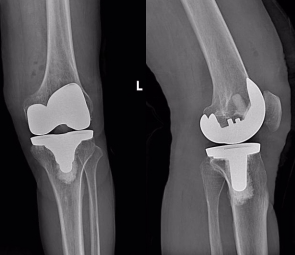

术前准备完善后,北京大学第三医院关节外科专家李杨副主任医师来到延安为两位患者先后实施了左侧人工全膝关节表面置换术。术中见膝关节软骨磨损严重,克服了因下肢力线与畸形、骨质缺损、骨骼质量、肌肉萎缩、关节强直等引起的种植体的准确放置、韧带间的平衡和肢体对线的恢复等诸多难题,为他们顺利植入了仿生的人工假体。

全膝关节置换术是治疗终末期膝骨关节炎的一种有效且持久的治疗手段,通过将膝关节中的受损部分切除,使用仿真人工关节替代的手术方式,随着对膝关节生物力学研究的不断深入,膝关节假体设计理念不断更新,人工膝关节置换手术也日趋成熟。对于终末期骨性关节炎特别是伴有畸形的患者来说,全膝关节置换术是一种行之可靠的治疗手段。只要适应症选择正确,假体选择恰当,术中精细操作,术后早期积极主动功能锻炼,不仅能减轻患者的疼痛,重建关节功能,更能提高老年患者的生活质量。